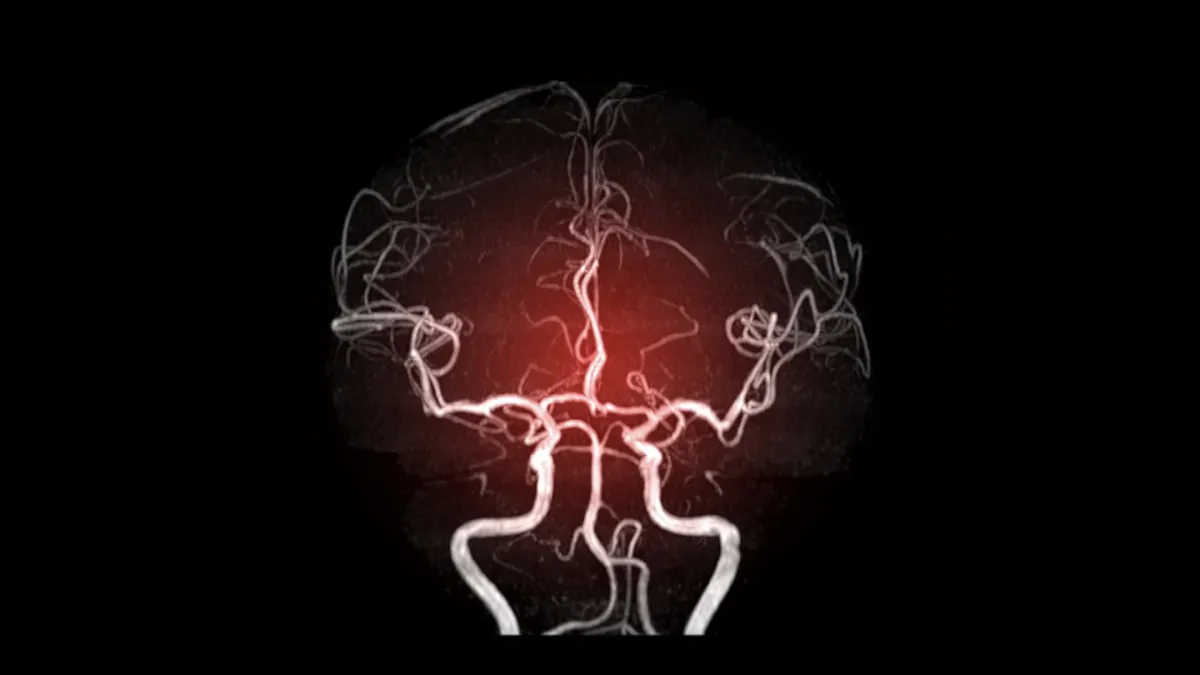

Diagnostika CVT je náročná, pretože klinický obraz je nešpecifický. Kľúčovú úlohu zohrávajú zobrazovacie metódy:

- CT venografia alebo MR venografia – metódy voľby na zobrazenie žilových splavov a žíl, ktoré potvrdia nepriechodnosť (oklúziu).